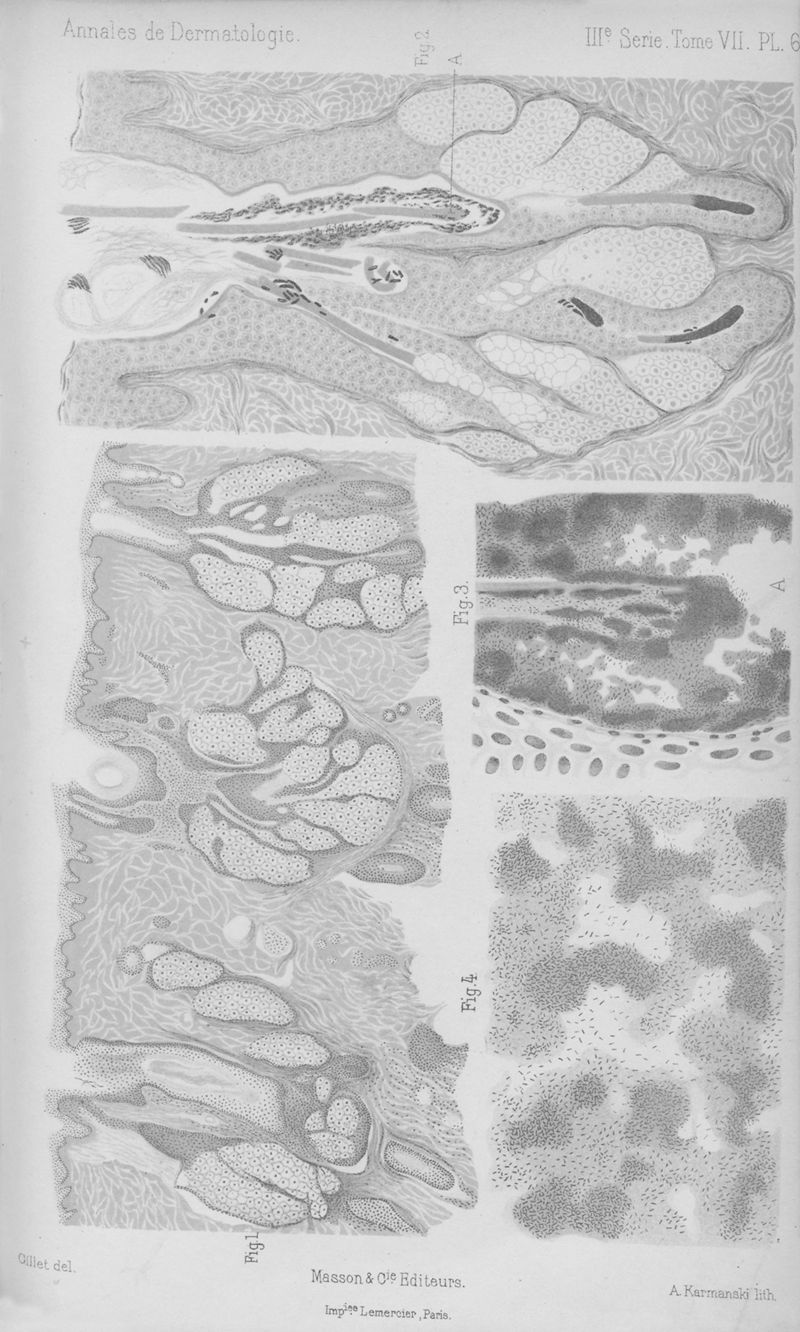

Annales de dermatologie et de syphiligraphie

3ème série, tome VII. - Paris : Masson, 1896.